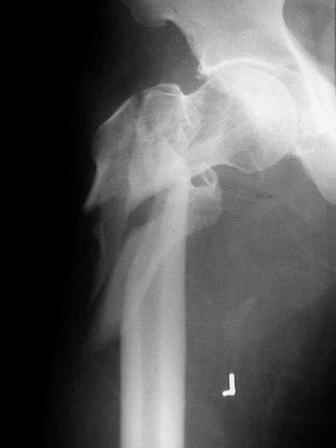

Re: Severely comminuted Trochenteric #

Few days ago I have posted an x-ray of severely comminuted Trochenteric # of Lt. Femur with sub-trochenteric extension of a male patient aged 65 years for opinion of fixation. Eight of you have kindly replied........

I choose Long Gamma Nailing and did it on 24.1.2006.

Now posting the post op x-rays for all of yours comments please. Don't hesitate to criticize me.